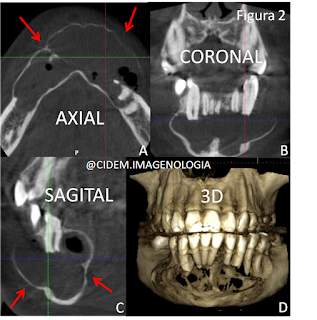

En asociación de los cortes

panorámico, axial, sagitales, coronales y reconstrucción 3D se observó imagen hipodensa definida y

corticalizada (Figura 2A) que produce reabsorción radicular externa de los

dientes adyacentes (Figura 2B y C) con expansión de las tablas (Figura 2A y D)

a predominio de cortical vestibular. La imagen presentaba signos tomográficos

de lesión odontogénica benigna, sugerente de Queratoquiste vs. Ameloblastoma.